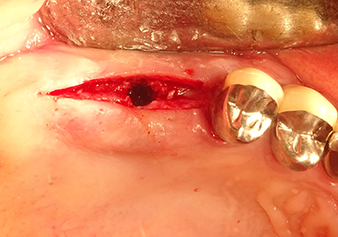

Dopo un controllo intermedio (Fig. 4) è stata eseguita un'ulteriore fase di preparazione (Fig. 5). Lo strumento idraulico Z35P è stato utilizzato in un secondo momento per sollevare la membrana sino alla posizione desiderata (Fig. 6 e 7). In seguito alla suddetta operazione, si è proceduto ad una ulteriore preparazione piezochirurgica della sede dell'impianto conclusasi con l'applicazione della fresa e della fresa a spallamento sul diametro dell'impianto di 4,8 mm. Il materiale di rinforzo (dimensione delle particelle di ca. 0,8 - 1,6 mm) è stato introdotto sotto la membrana di Schneider prima che venisse inserito l'impianto (Fig. 8).

Impianto e ricostruzione protesica

L'impianto è stato inserito manualmente e molto lentamente affinché il materiale di rinforzo potesse essere spostato atraumaticamente nella direzione del seno mascellare (Fig. 9). Nel corso del processo, la membrana è stata nuovamente spinta in direzione craniale. Due mesi dopo, il sito chirurgico si era cicatrizzato senza irritazioni. A distanza di sei mesi, la radiografia mostra un sensibile aumento dell'opacità intesa come prima comparsa di un centro di ossificazione (Fig. 10). La ricostruzione protesica è stata realizzata con una corona in metallo-ceramica.